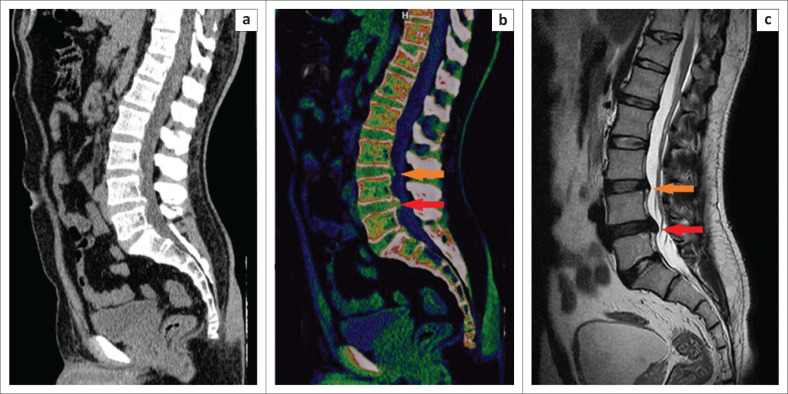

Method: The retrospective study included 84 patients between 01 July 2023 to 31 December 2023 who underwent DECT and 1.5-T MRI within 1 week. Four radiologists, blinded to the clinical and MRI information, independently evaluated the standard CT series and DECT series with ED reconstructions for lumbar disc herniation and spinal nerve root impingement. The gold standard for comparison was lumbar spine MRI, and diagnostic accuracy was measured with sensitivity and specificity.

Results: MRI revealed 417 lumbar disc herniations. Dual-energy computed tomography with ED reconstruction showed higher sensitivity (86.36% [532/616] vs. 57.79% [356/616]) and specificity (96.86% [1019/1052] vs. 95.82% [1008/1052]) for the detection of lumbar disc herniation compared to standard CT.

Conclusion: Dual-energy computed tomography with ED reconstruction shows better diagnostic performance for the detection of lumbar disc herniation compared to standard CT and can be a useful alternative imaging modality when MRI is contraindicated or unavailable.